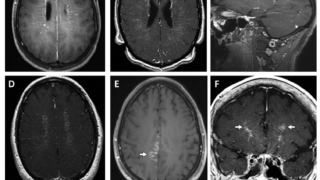

一方、Leber遺伝性視神経症における連続的な無痛性視力低下、Leigh症候群における発達退行と対称的な基底核信号異常、MELAS症候群における脳卒中様エピソードなどは強くミトコンドリア病を疑う所見となる。

本邦のm.3243A>G変異を伴うミトコンドリア糖尿病113例を解析した報告では、平均BMI18.6、糖尿病の発症は32.8±12.4歳、母方の糖尿病の家族歴は68%、インスリン治療が86.1%、抗GAD抗体は陰性。診断からインスリン治療開始まで平均3年。両側の感音性難聴を92%に認め、難聴の平均診断年齢は33.2歳。母方の難聴の家族歴は82%。他の臓器病変は心筋症30.4%、心伝導障害26.8%、神経筋疾患23.2%(MELAS12.5%、外眼筋麻痺8.9%)、基底核石灰化71.4%。